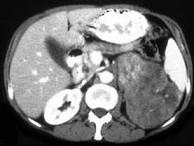

问题 女,43岁,满月脸、皮肤紫纹、月经不规则3月余,请结合所提供图像,作出诊断()

选项 A.左肾上腺腺瘤 B.左肾上腺嗜铬细胞瘤 C.左肾上腺转移瘤 D.左肾上腺腺癌 E.左肾上腺增生

答案 D